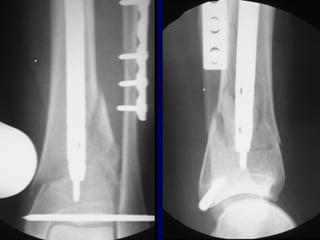

• 98.

Plating of TibialFractures • Narrow 4.5mm DCP plate can be used for shaft fractures • Newer periarticular plates available for metaphyseal fractures

• 99.

Technique of TibialPlating • Anterior longitudinal incision allows placement of plate on medial border of tibia • 4.5mm LCDCP plate secured to bone on distal fragment • Butterfly fragment can be secured with interfragmentary screw • The AO articulating tension device can be secured to proximal part of plate to aid reduction • With fracture reduced, screws placed through plate on either side of fracture

• 100.

Technique of TibialPlating • Newer alternative is use of limited incisions and subcutaneous plating- requires indirect reduction of fracture

• 101.

Advantages of Plating Anatomicreduction usually obtained In low energy fractures 97% very good/good results have been reported* *Ruedi et al. Injury vol 7

• 102.

Disadvantages of Plating •Increased risk of infection and soft tissue problems, especially in high energy fractures • Higher rate hardware failure than IM nail